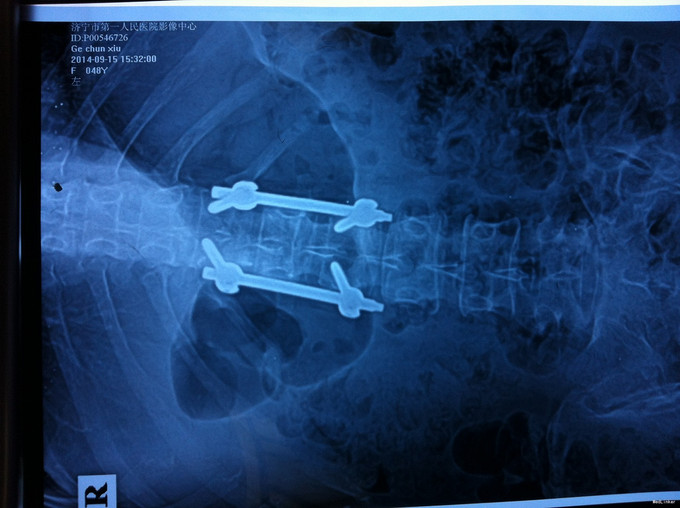

专科查体无下肢神经损伤表现:腰部叩痛,腰部活动受限,双下肢感觉无异常,双下肢肌力4-5级,双侧膝腱反射++,跟腱反射+,双侧巴氏征阴性, X-ray:腰1椎体骨折,累及前中柱,腰3椎体骨折。CT:腰1、3椎体骨折,累及中柱。MR:腰1、3骨折,新鲜骨折。影像学检查提示腰1椎体骨折较重。

诊断:腰椎骨折 腰1、3椎体 处理:1、完善相关辅助检查,明确诊断,有无手术指证; 2、完善手术评估,有无手术禁忌,手术风险及并发症; 3、在全麻下行腰1椎体后路撑开复位内固定术,腰3椎体压缩较轻,可卧床保守治疗。